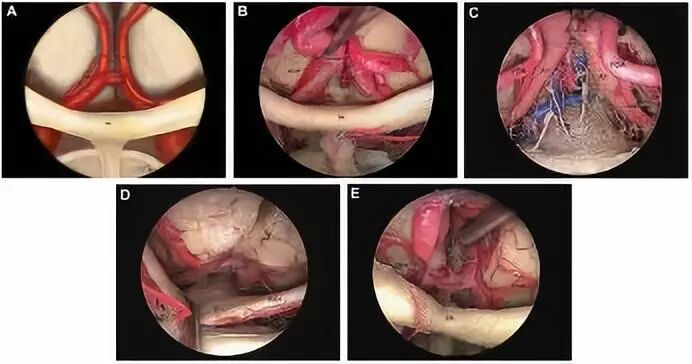

结果显示,20例(80%)标本中前交通动脉位于视交叉后半部分上方,5例位于视交叉前半部分上方(图1)。回返动脉从大脑前动脉A1段发出,在进入前穿质之前分成几个分支,其走行与同侧的ACA-A1段平行。根据RAH与A1段的空间关系分为三种类型:RAH位于A1段前方占40%,位于A1段上方占22%,位于A1段后方占38%。眶额动脉通常从ACA的A2段发出,越过嗅束和直回,达额叶的眶面。嗅束的近端三分之一是FOA越过的最常见部位,其次是中三分之一。额极动脉从ACA的A2段发出,也可与FOA共干起源(图2、3)。作者对RAH、FOA和FPA的直径、三者的起源部位至前交通动脉的距离等解剖关系进行数据统计(表1~3),作为内镜下经鼻入路的解剖学基础。

图2. A.内镜下显示,RHA最常见的起源部位是A1或A1-A2交界处;RHA在A1的上、前或后与A1平行走行;B.内镜下显示,右侧RHA位于A1的上方,而左侧RHA则位于A1的前方;C.内镜下显示,左侧RAH位于左侧A1的前面;该照片显现粗大的胼胝体下动脉(SbA);D.内镜下显示,右侧FOA起源于A2段,与嗅束的近侧1/3处相交叉;RAH在左侧位于A1的前方;E.内镜下显示,FOA和FPA的共干起源。